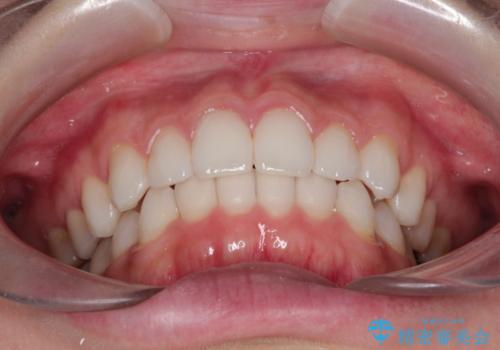

使用時間を守っていただけたので、スムーズに治療を終わることができました。

1周目が終わり、かなり綺麗になりましたがもう少し納得出来るまで続けたいという要望に答えてくださり、今2周目を終え本当に満足いく結果になりました。ありがとうございます。矯正を通して歯は意外と簡単に動くのだなと身をもって感じたのでこれからもリテーナーを怠らずつけ続けたいと思います。